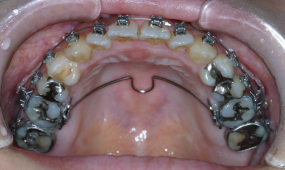

| 装置名 | マルチブラケット装置、歯科矯正用アンカースクリュー、パラタルバー |

マルチブラケット装置にて上下の歯を非抜歯で配列し、歯科矯正用アンカースクリューを用いて上下の奥歯の圧下(歯を歯肉方向に埋め込ませる動き)を図ります。下の顎を反時計回り(口が閉じる方向)に回転させることにより、前の歯の咬合接触を獲得します。舌の癖に対しては口腔筋機能訓練(MFT)とスマイルトレーニングを徹底し、機能的・審美的回復を図ります。

上顎・正面・下顎

- 治療前

- 治療中

- 治療後